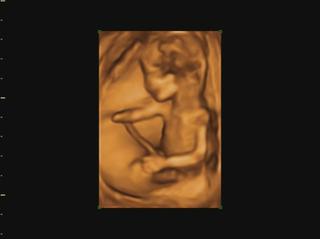

už som objednaná aj na 3D do KE... konečne môžem kľudne spávať 😀 😀 😀

@veronika1417 medzi 3d a 4d nie je skoro žiadny rozdiel, takže všade kde robia 3d robia aj 4d, lebo to štvrte D znamena čas,4d-real time, že mimi vidiš v realnom čase ako sa hybe.čiže stale je to 3d-trojdimenzionalne videnie babatka v 4d-realnom čase 😉

@luci66 juuuj Ty mas ake super informacie 🙂 to som vobec nevedela ze sa meria nosova kosticka a sijove prejasnenie, ten doktor na sone je taky dilino cely cas je ticho len tam znudene sedi a mna ide slaktrafit a trpnem ci je vsetko v poriadku ☹ ja som si veru sono uzila velakrat lebo sme dost lezali v nemocnici ale uz je to oki. Teraz uvidim miminko az 30.6 co je strasne daleko ☹ to uz budeme v 20 tyzdni 🙂 takze aj obrazok by mal byt uz kraaasny 🙂 mozno si dam aj ten 3D viem ze v Ba robia aj 4D ale v NR len 3D